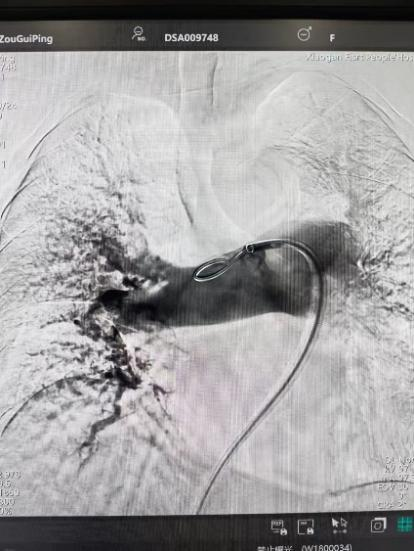

術(shù)前

手術(shù)在局部麻醉下進(jìn)行,團(tuán)隊通過股靜脈穿刺,將專用抽栓導(dǎo)管精準(zhǔn)送達(dá)肺動脈栓塞部位,利用負(fù)壓抽吸技術(shù)成功清除大量血栓;隨后,在血栓局部精準(zhǔn)灌注溶栓藥物,進(jìn)一步溶解殘余血栓,恢復(fù)肺部血流灌注;同時,為防止下肢深靜脈血栓再次脫落引發(fā)肺栓塞,團(tuán)隊為患者置入下腔靜脈濾器,整個手術(shù)歷時約1小時。術(shù)后,鄒婆婆呼吸困難癥狀即刻得到緩解,血氧飽和度顯著提升,右心負(fù)荷明顯減輕,目前身體狀況正在逐步恢復(fù)中。